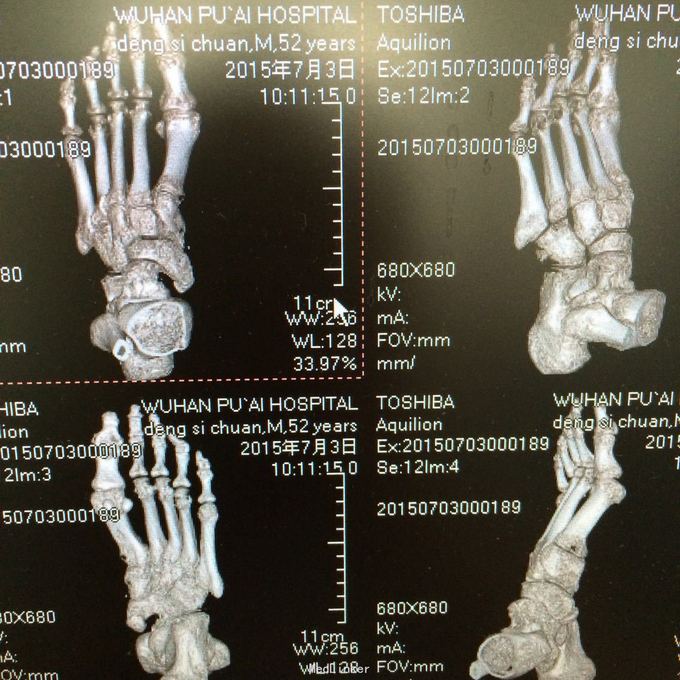

患者男,52岁。因“左跟肿痛不适二年余,加重一月”入院。 既往无特殊

左跟骨轻度肿胀,跟骨部压痛阳性,距下关节活动僵硬。左足背动脉搏动可触及,左足各趾活动、感觉正常,末梢血循环情况良好。 门诊资料:医院MRI检查(201506231473)示:“中距下关节骨质破坏,跟骨关节面死骨形成”。X线片示左跟骨上部骨质密度减低。

初步诊断:左跟骨感染?左跟骨占位性病变 诊疗计划:1.完善相关检查 2.卧床休息,暂不负重,对症支持治疗。 3.请示上级医师指导治疗。